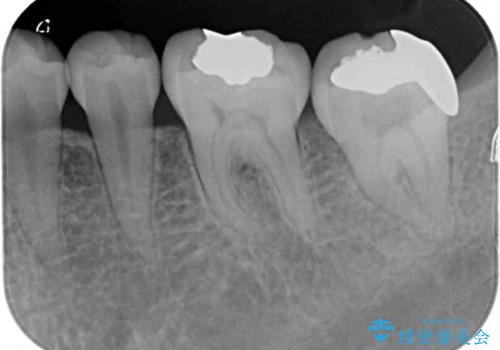

- 近医にてむし歯治療を行った後に痛みが出たとのことで来院された患者様です。

左下奥歯は術後から咬合時の痛みが発現し、来院時には脈を打つような痛みが認められました。

診察の結果、神経を取り除く必要があると判断されたため根管治療を行いました。

その後、左上の奥歯にも咬合時の痛みが認められ、レントゲン写真より歯内の神経が失活していることが分かりました。

2歯ともに根管治療を行い、その後はオールセラミッククラウンにて補綴治療を行うこととしました。